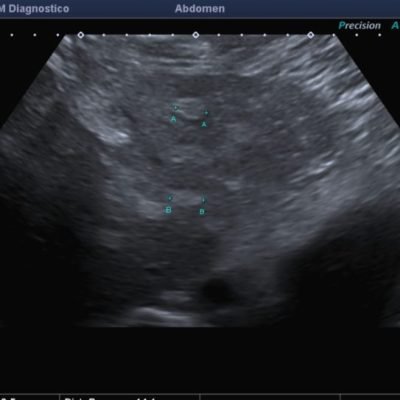

El médico de referencia le indica nueva ecografía de control, donde se observan múltiples y extensas lesiones focales hepáticas hiperecogénicas, redondeadas y confluentes, las cuales predominan en adyacencia a venas supra hepáticas, sin condicionar efecto de masa y sin alteración de la superficie hepática(fig. 1 y 2). Ante la valoración con Doppler color no presenta patrón de flujo peri ni intralesional y respeta el calibre de las venas supra hepáticas(fig. 3 y 4). Dada las características ecográficas se sospecha esteatosis focal multinodular confluente como principal diagnóstico presuntivo, siendo los diagnósticos diferenciales patologías de naturaleza infecciosa, tumoral o metastásica.